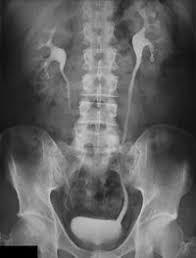

Estudios de contraste

Pielograma (o pielografía) intravenoso: probablemente se le pedirá que no coma ni beba nada por aproximadamente 12 horas antes de este estudio, y debe tomar laxantes para vaciar el intestino. Para el estudio en sí, usted se acuesta sobre una mesa para una serie de radiografías. Luego se le suministra el tinte de contraste por medio de una vena del brazo. Los riñones eliminan el tinte de contraste del torrente sanguíneo y este ingresa en el tracto urinario. Se toma otra serie de radiografías en los siguientes 30 minutos para obtener imágenes del tinte a medida que se mueve a través de los riñones y fuera de su cuerpo. Se puede aplicar presión en el vientre para ayudar a hacer que la imagen sea más clara. Una vez que el tinte de contraste llega a la vejiga, se le pedirá que orine mientras se toma otra radiografía.